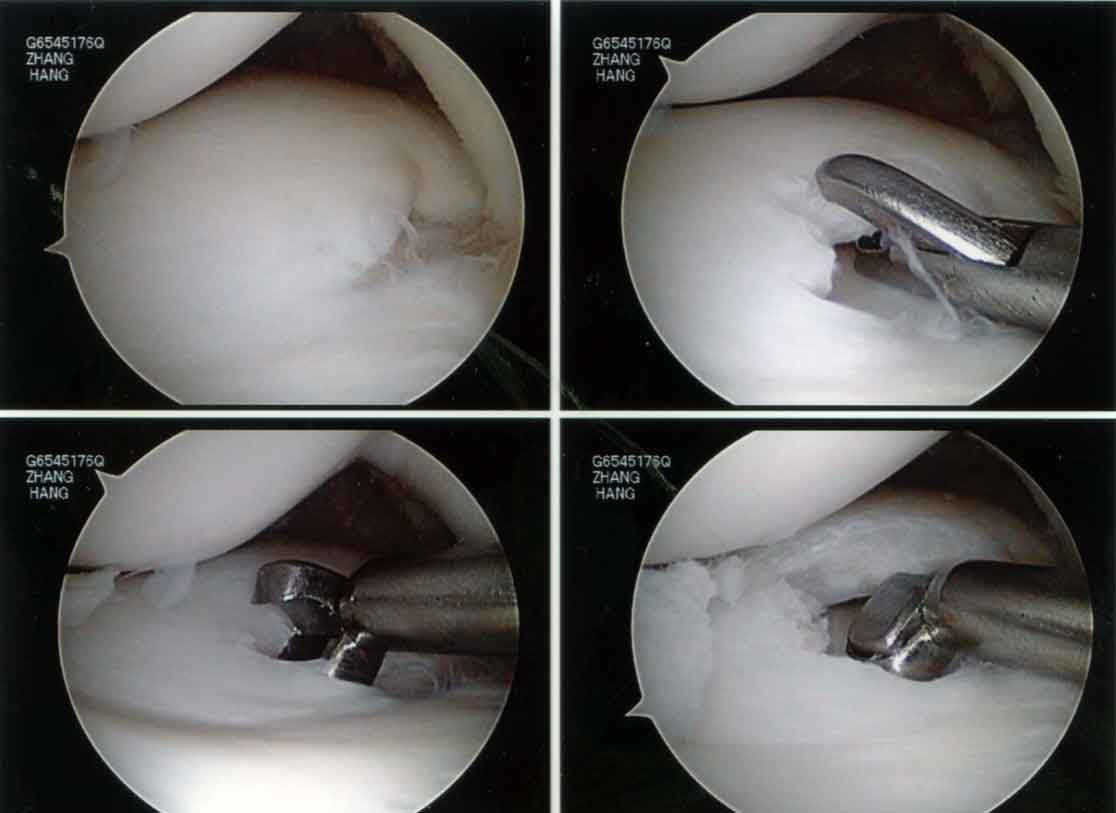

The discoid lateral meniscus was torn and detached from the capsule and has buckled into the inside of the joint. It looked like this:

As the patient was very young, I decided to reshape the discoid lateral meniscus and repair the torn parts back to the capsule. This is a reconstruction of the discoid lateral meniscus. I feel that this is a much better option than cutting the lateral meniscus away. Removing almost the entire lateral meniscus will definitely lead to a lot of pain and disability in this young lady.

Firstly the discoid portion of the lateral meniscus was removed arthroscopically as shown: